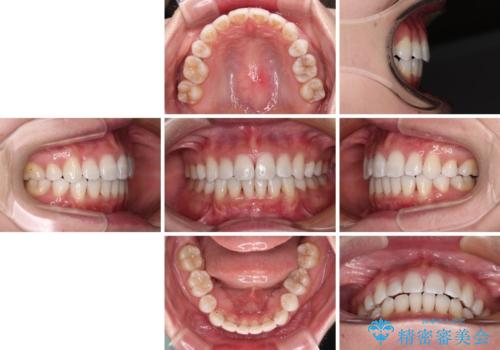

- 口元の突出感と口の閉じにくさを気にして来院された患者様です。

上下左右第一小臼歯4本を抜歯し、ワイヤー装置にて口元を引っ込めるよう矯正治療を行うこととしました。

2年~2年半が治療期間の目安でしたが、順調に治療が進み、1年9か月で満足のいく歯列となりました。